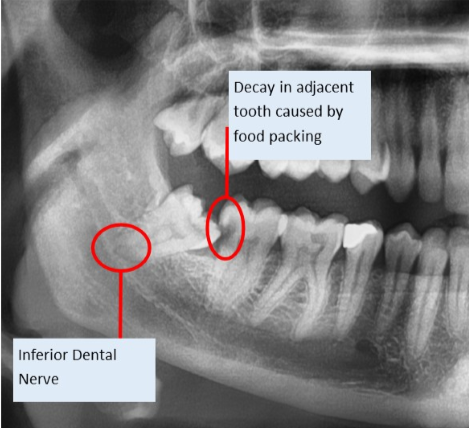

Sometimes wisdom teeth do not have suffiecient room to erupt fully, these are called impacted. Impacted teeth can sometimes lead to painful infections as well as food packing, which in turn can lead to decay. Sometimes this decay is in the adjacent tooth.

Lower wisdom teeth lie in close proximity to a nerve that supplies sensation to your lower lip, chin and teeth (Inferior Dental Nerve) as well as a nerve that supplies sensation to your tongue.